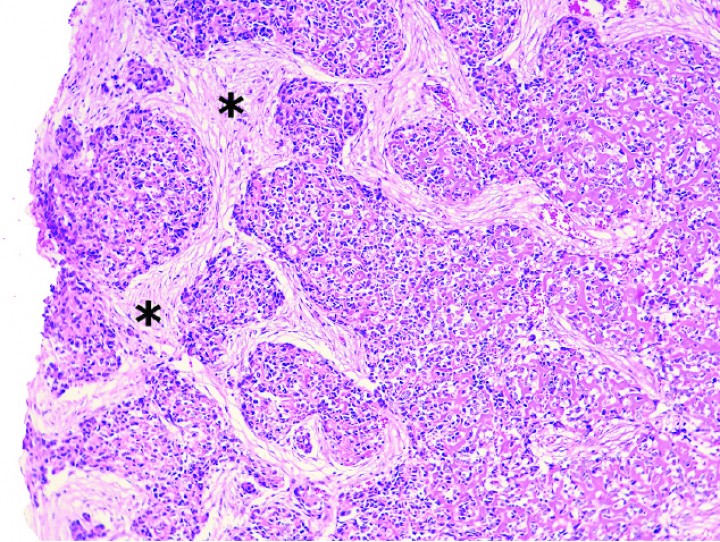

Histológicamente, estos condrosarcomas se caracterizaban por una proliferación de células poliédricas a fibrohistiocíticas o, más raramente, fusiformes dispuestas en nidos, haces o de forma sólida, con depósitos dispersos intercelulares de matriz basófila o anfofílica densa y, en algunos casos, matriz fibrilar eosinofílica que mostraba osificación endocondral o mineralización variable (Figs. 5, 6 y 7); ocasionalmente, se apreciaban zonas con estroma fibroso (Fig. 8).

<p>Cobaya 4. Imagen microscópica de zonas con haces de estroma fibroso (asteriscos) en un condrosarcoma. (Hematoxilina y eosina, x120).</p>

Figura 8

Cobaya 4. Imagen microscópica de zonas con haces de estroma fibroso (asteriscos) en un condrosarcoma. (Hematoxilina y eosina, x120).